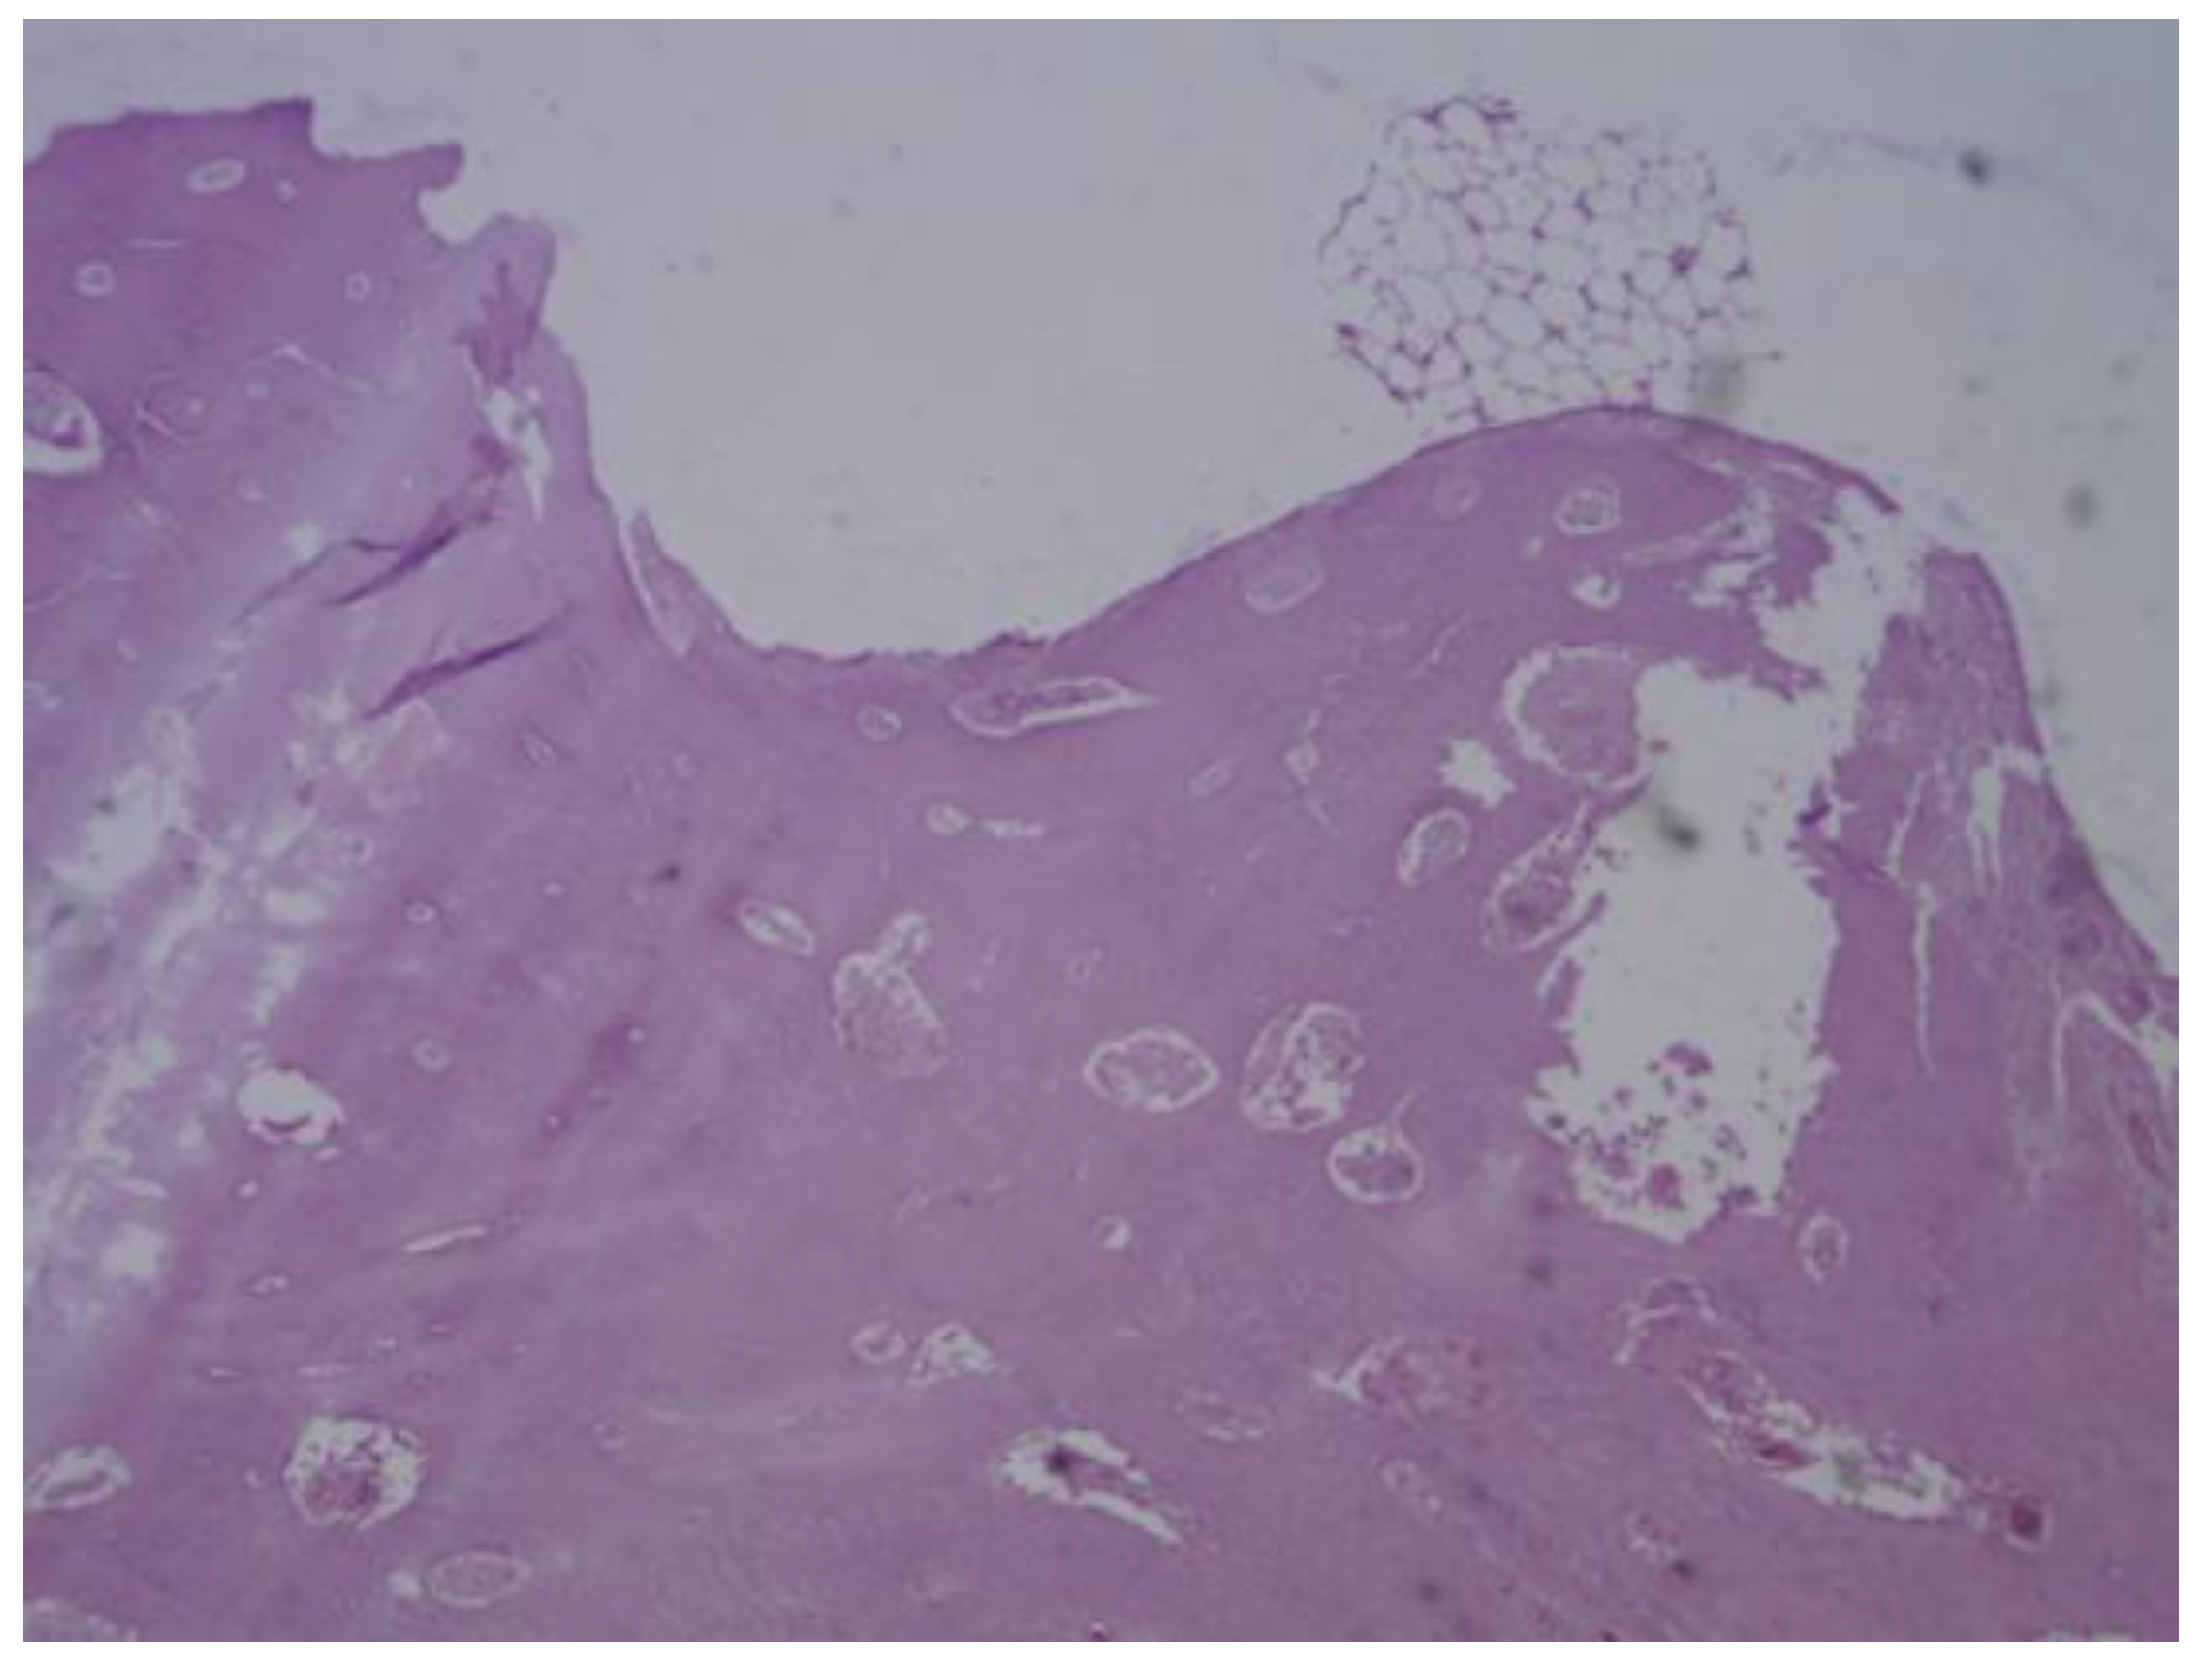

Figure 26. PLDLLA periprosthetic fibrosis is mild, indicating a moderate tissue response without excessive fibrous encapsulation.

PLDLLA: In this case, histological analysis reveals absence of osseointegration, indicating that no direct union has been established between the PLDLLA implant and the surrounding bone tissue. However, fibrointegration is present, suggesting the presence of fibrous tissue at the bone-implant interface. Periprosthetic fibrosis is mild, indicating a moderate tissue response without excessive fibrous encapsulation. Neovascularization is high, reflecting significant formation of new blood vessels in the area adjacent to the implant. Focal osteoid presence is observed, indicating a limited degree of osteogenic activity at the implant interface. (Figure 26)